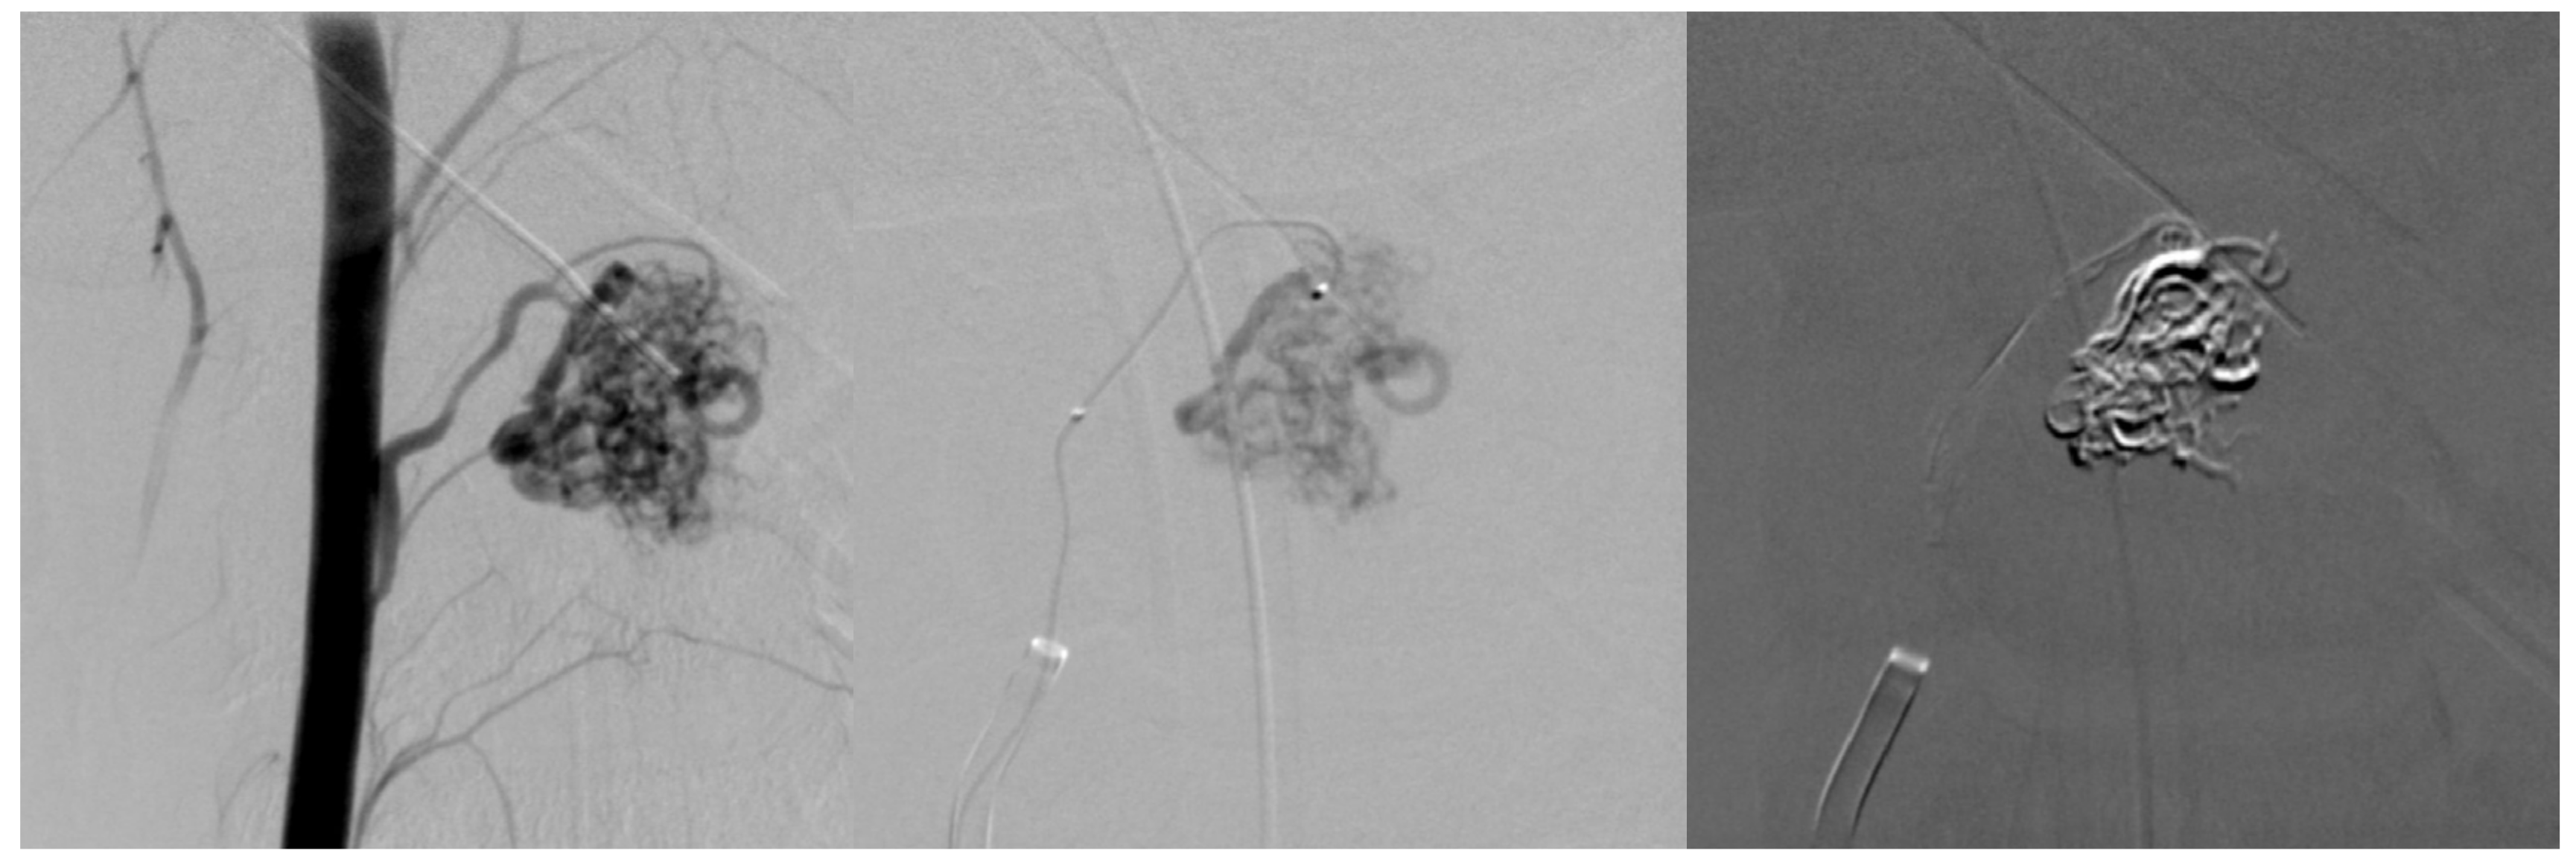

7.2. Second Episode (2020)

7.3. Third Episode (2023)